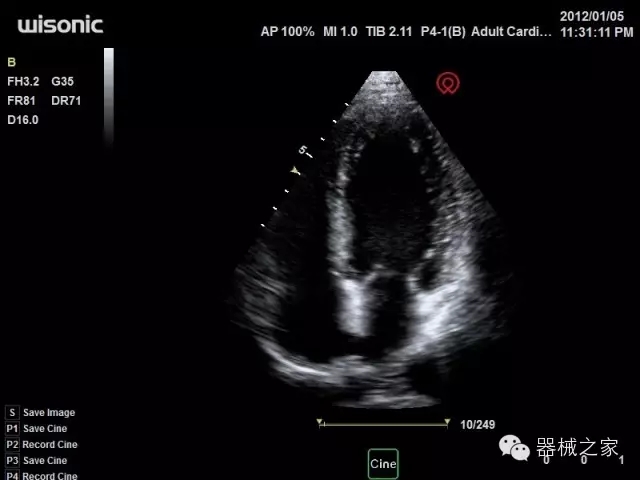

經(jīng)典產(chǎn)品:S8EXP

臨床圖片賞析

產(chǎn)品特點

優(yōu)異的成像技術(shù)

·亞陣元技術(shù):獨有的亞陣元技術(shù),對獨立晶片做二次切割,減少旁瓣偽像,增加臨床診斷的準(zhǔn)確性;

·μ-Scan微米成像技術(shù):開立獨有的μ-Scan技術(shù),還原出真實細(xì)膩、層次對比優(yōu)異的二維圖像;

·倒相諧波成像技術(shù):倒相諧波技術(shù)在去除基波信號的基礎(chǔ)上獲取兩倍二次諧波信號,提高組織圖像的對比分辨力;

·智能微血流成像技術(shù):智能微血流捕捉技術(shù)可以提取出隱藏在背景噪聲中的弱血流信號,大大提高低速血流的敏感性;

全面的臨床解決方案

超聲科常規(guī)領(lǐng)域應(yīng)用

·移植S40高端臺式彩超高端平臺技術(shù),滿足超聲科腹部、淺表、婦產(chǎn)科、心血管、肌骨等應(yīng)用,提供超聲科完美解決方案;

·實時的彈性成像技術(shù):提高了小器管(乳腺,甲狀腺、淺表軟組織腫瘤等)疾病鑒別診斷;

·IMT血管內(nèi)中膜自動測量:為血管性疾病評估提供了有效的評估手段;

·心功能綜合指數(shù)(TEI指數(shù)):用于左、右心室整體心臟收縮舒張功能評估的測量方法;

·全方位可調(diào)M型:有利于更好的觀察心腔大小及室壁階段性運動的異常情況;

·組織多普勒成像(TDI):TDI可定量評價心肌運動,判斷是否有局部病變,還可評價早期的舒張功能;

·高效3D/4D成像技術(shù):高速的4D幀頻,豐富的3D成像模式,智能斷層切片功能;

POC領(lǐng)域解決方案

·外觀小巧;

·穿刺增強技術(shù):可有效提高進(jìn)針區(qū)圖像分辨率,提高進(jìn)針亮度,全面提高一次性穿刺的成功率;

全面的術(shù)中探頭解決方案

·小凸探頭:開放性手術(shù),實時監(jiān)測病灶位置,提高手術(shù)成功率,可應(yīng)用于麻醉科、肝膽外科、腫瘤外科、神經(jīng)外科、泌尿外科等手術(shù);

·L型線陣探頭:高分辨率圖像,清晰顯示病灶位置,提高手術(shù)成功率,可應(yīng)用于麻醉科、胸外科、肝膽外科、腫瘤外科、神經(jīng)外科、泌尿外科等應(yīng)用;

·MPTEE:經(jīng)食道探頭術(shù)中監(jiān)測,可測量心臟前負(fù)荷(左室舒張末期大小、右房大?。?、心排血量、后負(fù)荷、收縮功能、室壁運動分析、肝靜脈血流(與中心靜脈壓相關(guān))等,術(shù)后還能及時評估手術(shù)效果評估;

·獨有的大角度及實時溫控技術(shù),能同一切面顯示宮頸及宮體,有效減低了患者的痛苦,及保護(hù)粘膜保證了醫(yī)療安全;

高效的人機(jī)工程學(xué)設(shè)計

·15‘’高清醫(yī)用顯示器;

·內(nèi)置雙探頭接口;

·可升降臺車,1拖3探頭擴(kuò)展器;

·m-Tuning一鍵優(yōu)化;